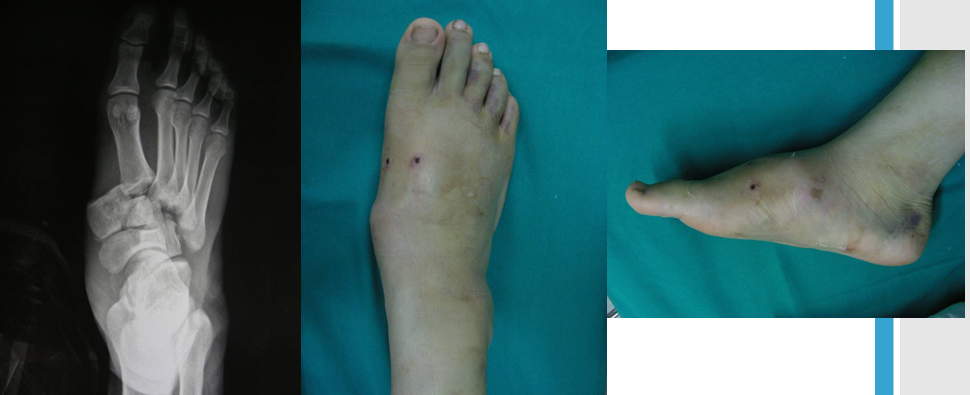

中足疼痛、负重困难;足背肿胀;由于可能的自行复位可致畸形多变。

足底瘀青可出现较晚;跖跗关节局部压痛;轻度跖屈、背伸和旋转应力可显示不稳。

影像学诊断

在足正位X线上,第1、2、3跖骨的内外侧缘分别和它相对应的楔骨的内外侧缘呈一直线排列;第一、二跖骨基底间隙和内中楔骨间隙相等。

30°斜位上:1、第四跖骨内侧缘和骰骨内侧缘连续成一条直线2、第三跖骨内侧缘和外侧楔骨内侧缘连续成一条直线3、第二、三跖骨基底间隙和内、中楔骨间隙相等。

侧位上,跖骨不超过相应楔骨背侧缘。从远端的跖骨经过跖跗关节到近端的跗骨,应该是一条不间断的连线

2005年Pearse等提出“ABC”的方法来阅读足部X 线片, 以减少中、前足的漏诊。 A ( alignment)检查跖骨与相应楔骨的对应线 B ( bone)检查每一块骨的轮廓 C ( congruity )检查整体一致吻合, 在正位片上观察内柱, 在斜位片上观察中、外柱。侧位片的常规检查可发现Lisfranc关节矢状面的半脱位及撕脱性骨折

特殊放射学检查应力位摄片:评价跖跗关节的稳定性负重位摄片:评价足的纵弓的稳定性,以及明确第1跖骨间隙的增宽 外侧斜位:诊断细微的第1跖骨间隙的增宽CT 扫描:诊断不明显的跖跗关节半脱位对照位摄片:明确细微的损伤